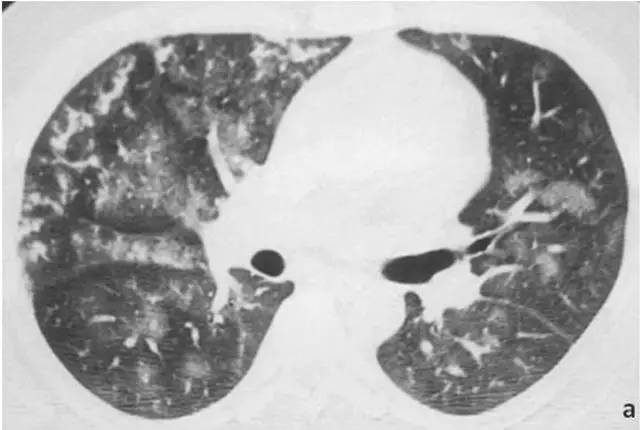

基本病史:男性,27 岁,反复发烧,伴有乏力、身体不适,曾口服抗生素治疗效果不好。行胸部高分辨率 CT 检查结果如下:

图 4 胸部高分辨率 CT 显示双肺弥漫性斑片状、结节状磨玻璃影,多以小叶中心性分布,符合肺泡出血的 CT 学表现